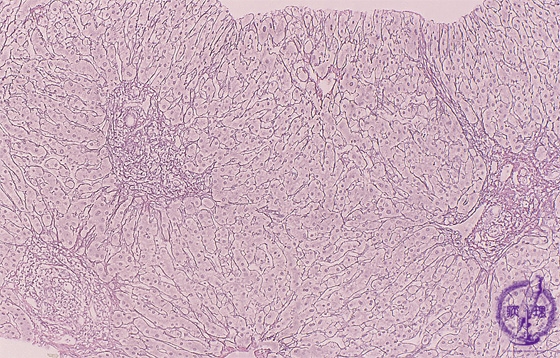

Microscopic image (silver stain, intermediate-power): There is portal fibrous expansion (red box) with varying degrees of bridging fibrosis (blue line).